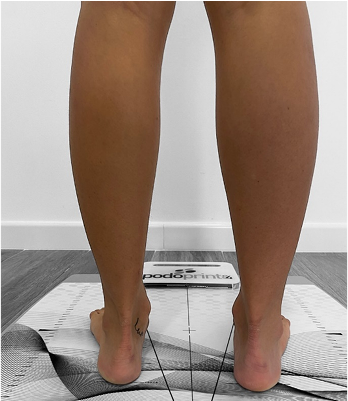

Algunas de las principales alteraciones en los pies de los niños son: pie plano, pie plano valgo, deformidades en los dedos, uñas encarnadas, causas de cojera en el niño, forma de caminar inestable con caídas y pies hacia dentro.

Técnicas específicas para el control y corrección de las patologías de los pies con moldes para la confección de plantillas ortopédicas.

Adaptación de plantillas personalizadas a medida en base a un diagnóstico.

Realización de técnicas exploratorias en camilla para detectar posibles asimetrías, disfunciones musculares, análisis del movimiento mediante sistema de análisis de la pisada con el objetivo de detectar alteraciones en la marcha que puedan ser causa de dolencias o posibles lesiones.